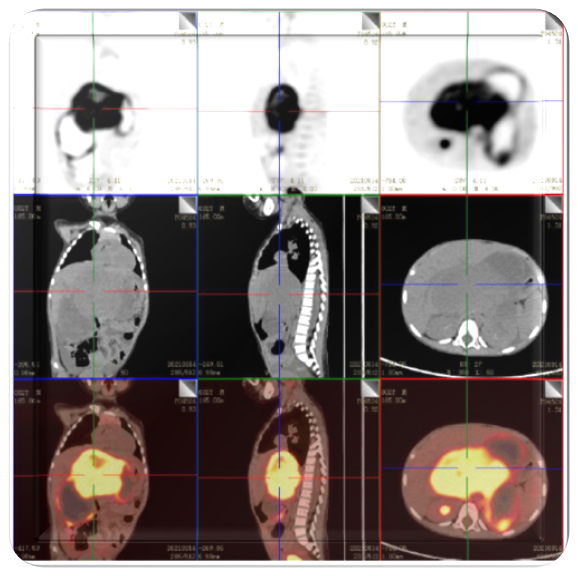

2022.09.12(第2周期后)

复查PET/CT:未见明确高代谢灶。

2023.02.13

腹膜后NB术后复查:未见异常。

PET/CT:未见明显异常。